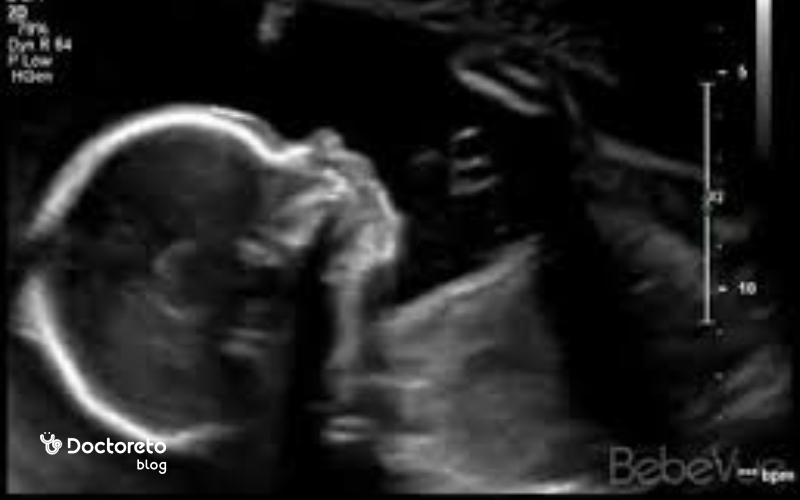

در هفته بیستوچهارم بارداری، جنین ظاهری شبیه نوزاد کامل دارد اما هنوز کوچکتر و لاغرتر است. قد او حدود ۳۰ سانتیمتر و وزنش نزدیک به ۶۰۰ تا ۷۰۰ گرم است. پوست جنین هنوز نازک و نیمهشفاف است و رگهای خونی از زیر آن دیده میشوند، اما بهتدریج با تشکیل چربی زیرپوستی ضخیمتر میشود. صورت او اکنون کاملاً قابلتشخیص است، پلکها، ابروها و مژهها رشد کردهاند و لبها شکل واضحتری پیدا کردهاند. اندامها متناسبتر شدهاند و حرکات دست و پا هماهنگتر است. در این زمان، جنین اغلب انگشتان خود را میمکد و نسبت به صداها واکنش نشان میدهد.

سونوگرافی در هفته بیست و چهارم بارداری

سونوگرافی آنومالی بهطور معمول در ۱۸–۲۱ (تا حداکثر ۲۲) هفته انجام میشود. اگر این بررسی در بازهٔ توصیهشده انجام نشده یا نگرانی بالینی وجود دارد، نوع و زمان ارزیابی تکمیلی باید طبق نظر پزشک تعیین شود. در این سونوگرافی، رشد جنین، وضعیت جفت، مقدار مایع آمنیوتیک و سلامت اندامهای اصلی مانند قلب، مغز، کلیهها و ستون فقرات بررسی میشود. همچنین موقعیت جنین، ضربان قلب و حرکات او ارزیابی میگردد تا از روند طبیعی رشد اطمینان حاصل شود. در صورت وجود هرگونه نگرانی یا علائم خاص، پزشک ممکن است سونوگرافی تکمیلی برای بررسی دقیقتر وضعیت جفت یا رشد جنین درخواست کند.